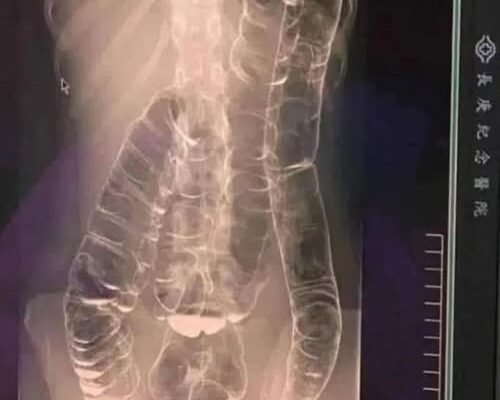

A saturated colon

When you don’t have regular bowel movements, waste builds up in the colon. The result: extra pressure that can cause pain, bloating , and, in severe cases, terrible complications.

- Colon distension: Over time, the colon weakens its elasticity and becomes increasingly difficult to remove stools.

- Bowel obstruction: In extreme cases, fecal matter can completely block the intestine, demanding emergency surgery .